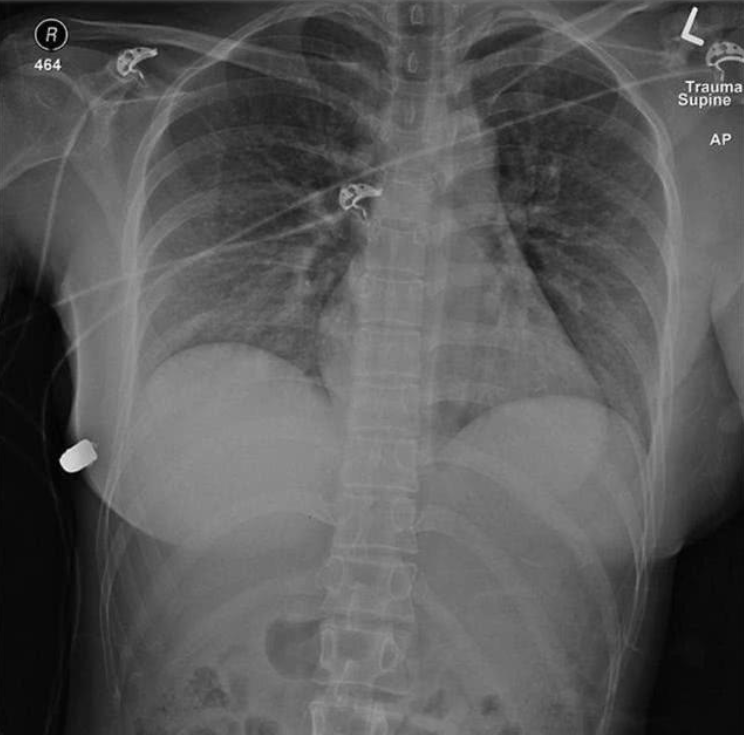

【『医学』假奶发威!女子胸部中弹“硅胶让子弹转弯”登上医学文献】加拿大多伦多一名30岁妇女2018年胸部中弹求医 。 但此案件如今再度受到外界关注 , 根据SAGE医学杂志上周发表的最新案例研究 , 该名女子隆乳的矽胶植入物可能让子弹偏离心脏 , 救回她的性命 。 医师认为 , 医学文献记载的乳房植入物挽救性命的案例本就不多 , 这更是第一起因矽胶植入物救回病人性命纳入医学文献的个案 。

▲该名女子受枪伤 , 左侧植入物明显受损 。 医师发现 , 假体明显被子弹穿透 。

综合CNN等外媒报导 , 这起事件发生在2018年加拿大多伦多 , 该名女子当时走在街头 , 在中弹后发觉左胸发热、疼痛 , 且身上出现血迹 , 随即前往医院急诊室寻求治疗 。 根据一系列医学检查后发现 , 她身上枪伤入口位在左侧乳房 , 但子弹最终却停留在身体右侧 , 且右侧肋骨骨折 , 左乳房的植入物明显受损 , 最终得出子弹自左胸转移至右胸的结论 。

「矽胶植入物改变子弹的轨迹」 , 外科医师麦伊凡努(Giancarlo McEvenue)认为 , 子弹射进她的皮肤后 , 矽胶植入物让子弹偏离原本轨道 , 使得子弹转移至右侧乳房 , 尽管右侧肋骨断裂 , 但也避免心脏被射穿的危机 , 「人体左侧有心脏和肺 , 如果子弹直接射进胸部 , 她的伤势会严重许多 , 甚至可能危害到性命 。 」

医师指出 , 该名女子除了枪伤、右侧肋骨断裂、矽胶植入物受损之外 , 并没有受到其他伤害 。 事后 , 医师移除植入物、冲洗伤口 , 同时开立短期抗生素疗程 , 辅助女子康复 。